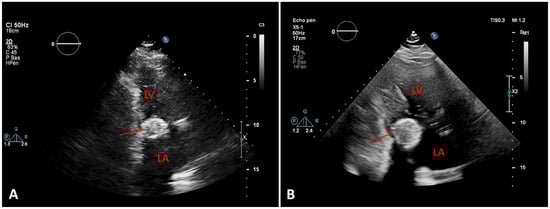

Figure 4.

A. Computed tomography (CT) scan, two chambers, at the time of diagnosis. B. CT scan, same view, 4 years later, showing the increasing size of the (arrows). LV = left ventricle, LA = left atrium

A routine transthoracic echocardiogram (TTE) performed 4 years previously, with a view to orthopaedic surgery, had revealed a cardiac mass attached to the posterior mitral annulus with a mitral mean gradient of 6 mm Hg (at a heart rate of 80 beats per minute). At that time cardiac magnetic resonance imaging (cMRI) and computed tomography (CT) were performed and the diagnosis of caseous calcification of the mitral annulus was established (

Table 1). The patient was admitted for oxygen supplementation and intravenous diuretics with rapid recovery ensuing in a few days. A TTE documented normal heart function but an increase in the size of the cardiac mass ( 46 mm × 31 mm compared with 36 mm × 27 mm 4 years before), the mean gradient across the mitral valve was unchanged at 6–7 mm Hg at a heart rate of 65 bpm (

Figure 5). A CT scan showed an increased size of the mass (

Figure 4). Due to the frailty of the patient and in accordance with her wish not to undergo any invasive treatment, surgery was not proposed. The patient was discharged before being admitted 2 months later for another episode of acute heart failure treated with intravenous diuretics. The therapeutic attitude was altered and at this time the patient was again discharged for ambulatory follow up for treatment adjustment and only symptomatic management if acute heart failure happens again.